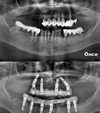

Implant tedavisi